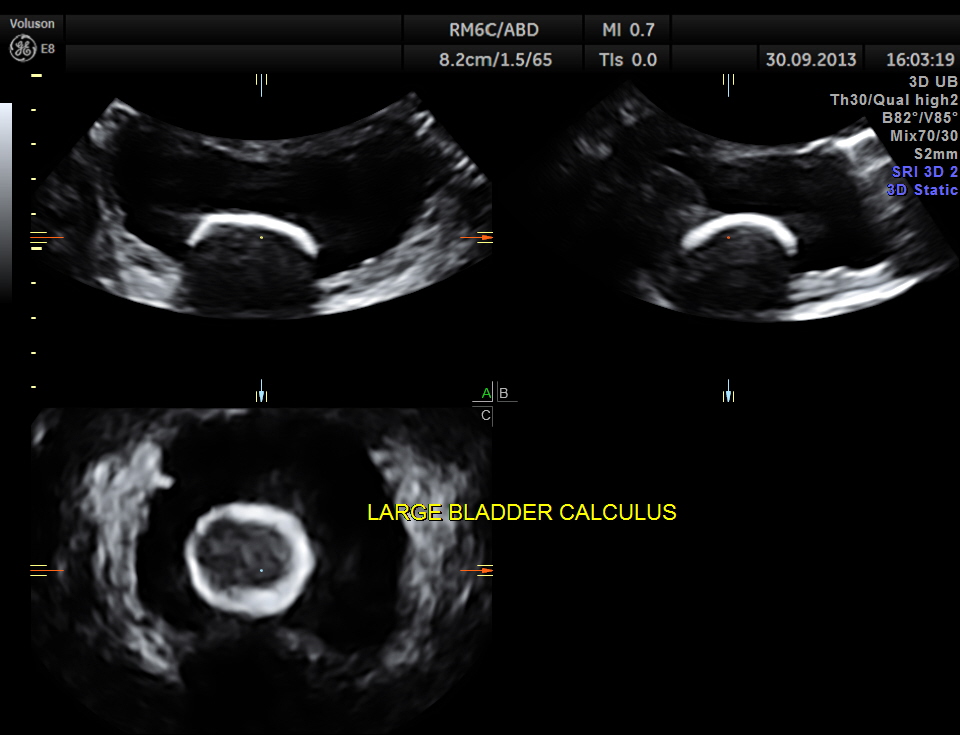

2 D and 3 D of the bladder calculus alone.

multi- planar view of the bladder calculus